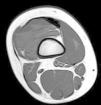

En revisiones posteriores, la paciente se encontraba asintomática entre los episodios de tumefacción articular, con controles de reactantes de fase aguda normales. Se solicitó una resonancia magnética de rodilla derecha, objetivándose una masa sólido-quística en la bursa suprarrotuliana que asociaba imágenes de calcificación sugestivas de flebolitos; se extendía al vastus intermedius y vastus lateralis y medía 83mm de eje mayor craneocaudal, compatible con malformación vascular de bajo flujo tipo venolinfática (figs. 1 y 2).

Se solicitó valoración por cirugía plástica que realizó biopsia incisional de la tumoración en vasto externo que confirmó la presencia de una malformación vascular de predominio venoso. Actualmente sigue revisiones por cirugía plástica y se está realizando esclerosis de la lesión.